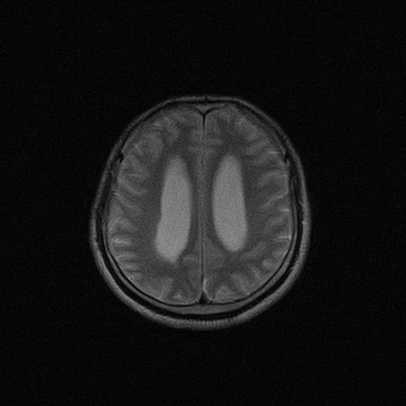

标题: MRI2064:少见病例。男性52,视力下降多年。 [打印本页]

标题: MRI2064:少见病例。男性52,视力下降多年。

四脑室区见混杂信号占位影,脑室系统扩张明显,临近结构显著受压称位,患者52岁,多考虑室管膜瘤可能性大

考虑第四脑室室管膜瘤并梗阻性脑积水;部分性空蝶鞍;左侧上颌窦粘膜下囊肿。